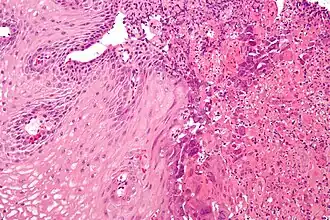

L’œsophagite est une inflammation de l’œsophage. Elle peut être aiguë ou chronique.

Types et causes

- Œsophagite inflammatoire : maladie de Crohn.

- Œsophagite immunoallergique : œsophagite à éosinophiles.